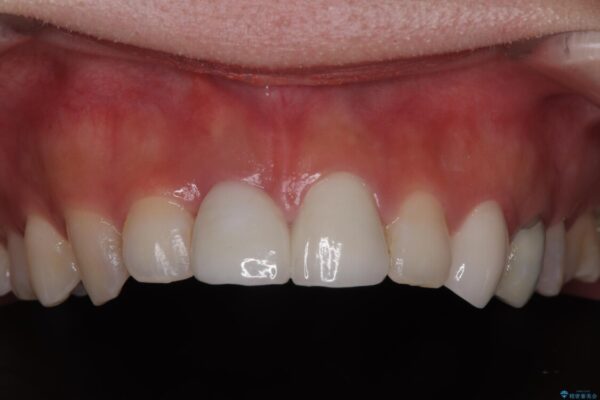

抜歯を避けられない場合でも、「即日でインプラント治療+仮歯装着」により見た目を損なわないで治療を終えることができました。

抜歯をしてインプラントを埋入してから、4か月で最終補綴物(オールセラミッククラウン)の装着まで終えることができ非常に満足いただきました。

治療後

• 「抜歯してブリッジ」と言われた20代女性が選んだ治療とは|たった4か月で自然な笑顔に抜歯即時インプラント+審美補綴の症例 治療後画像